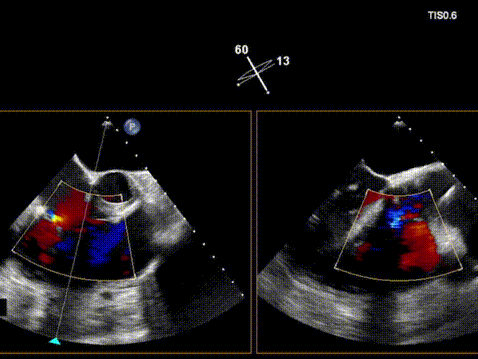

术前超声

术后超声